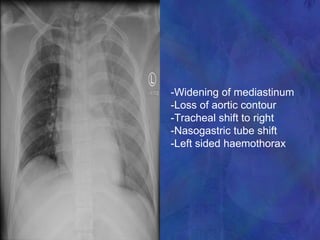

-Widening of mediastinum

-Loss of aortic contour

-Tracheal shift to right

-Nasogastric tube shift

-Left sided haemothorax

Traumatic Aortic Dissection/Rupture •Retrosternal or interscapular pain • Pain in lower back or one leg • Respiratory distress • Asymmetrical arm BPs • Upper extremity hypertension with • Decreased femoral pulses, OR • Absent femoral pulses • Dysphagia

-Widening of mediastinum -Lossof aortic contour -Tracheal shift to right -Nasogastric tube shift -Left sided haemothorax